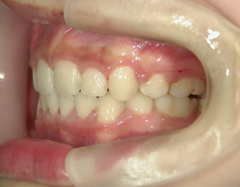

矯正歯科 治療途中 下顎の後退を改善する為、ツインフォースで下顎を前に出す

no.18_2196_治療中_右.jpgno.18_2196_治療中_正面.jpgno.18_2196_治療中_左.jpg